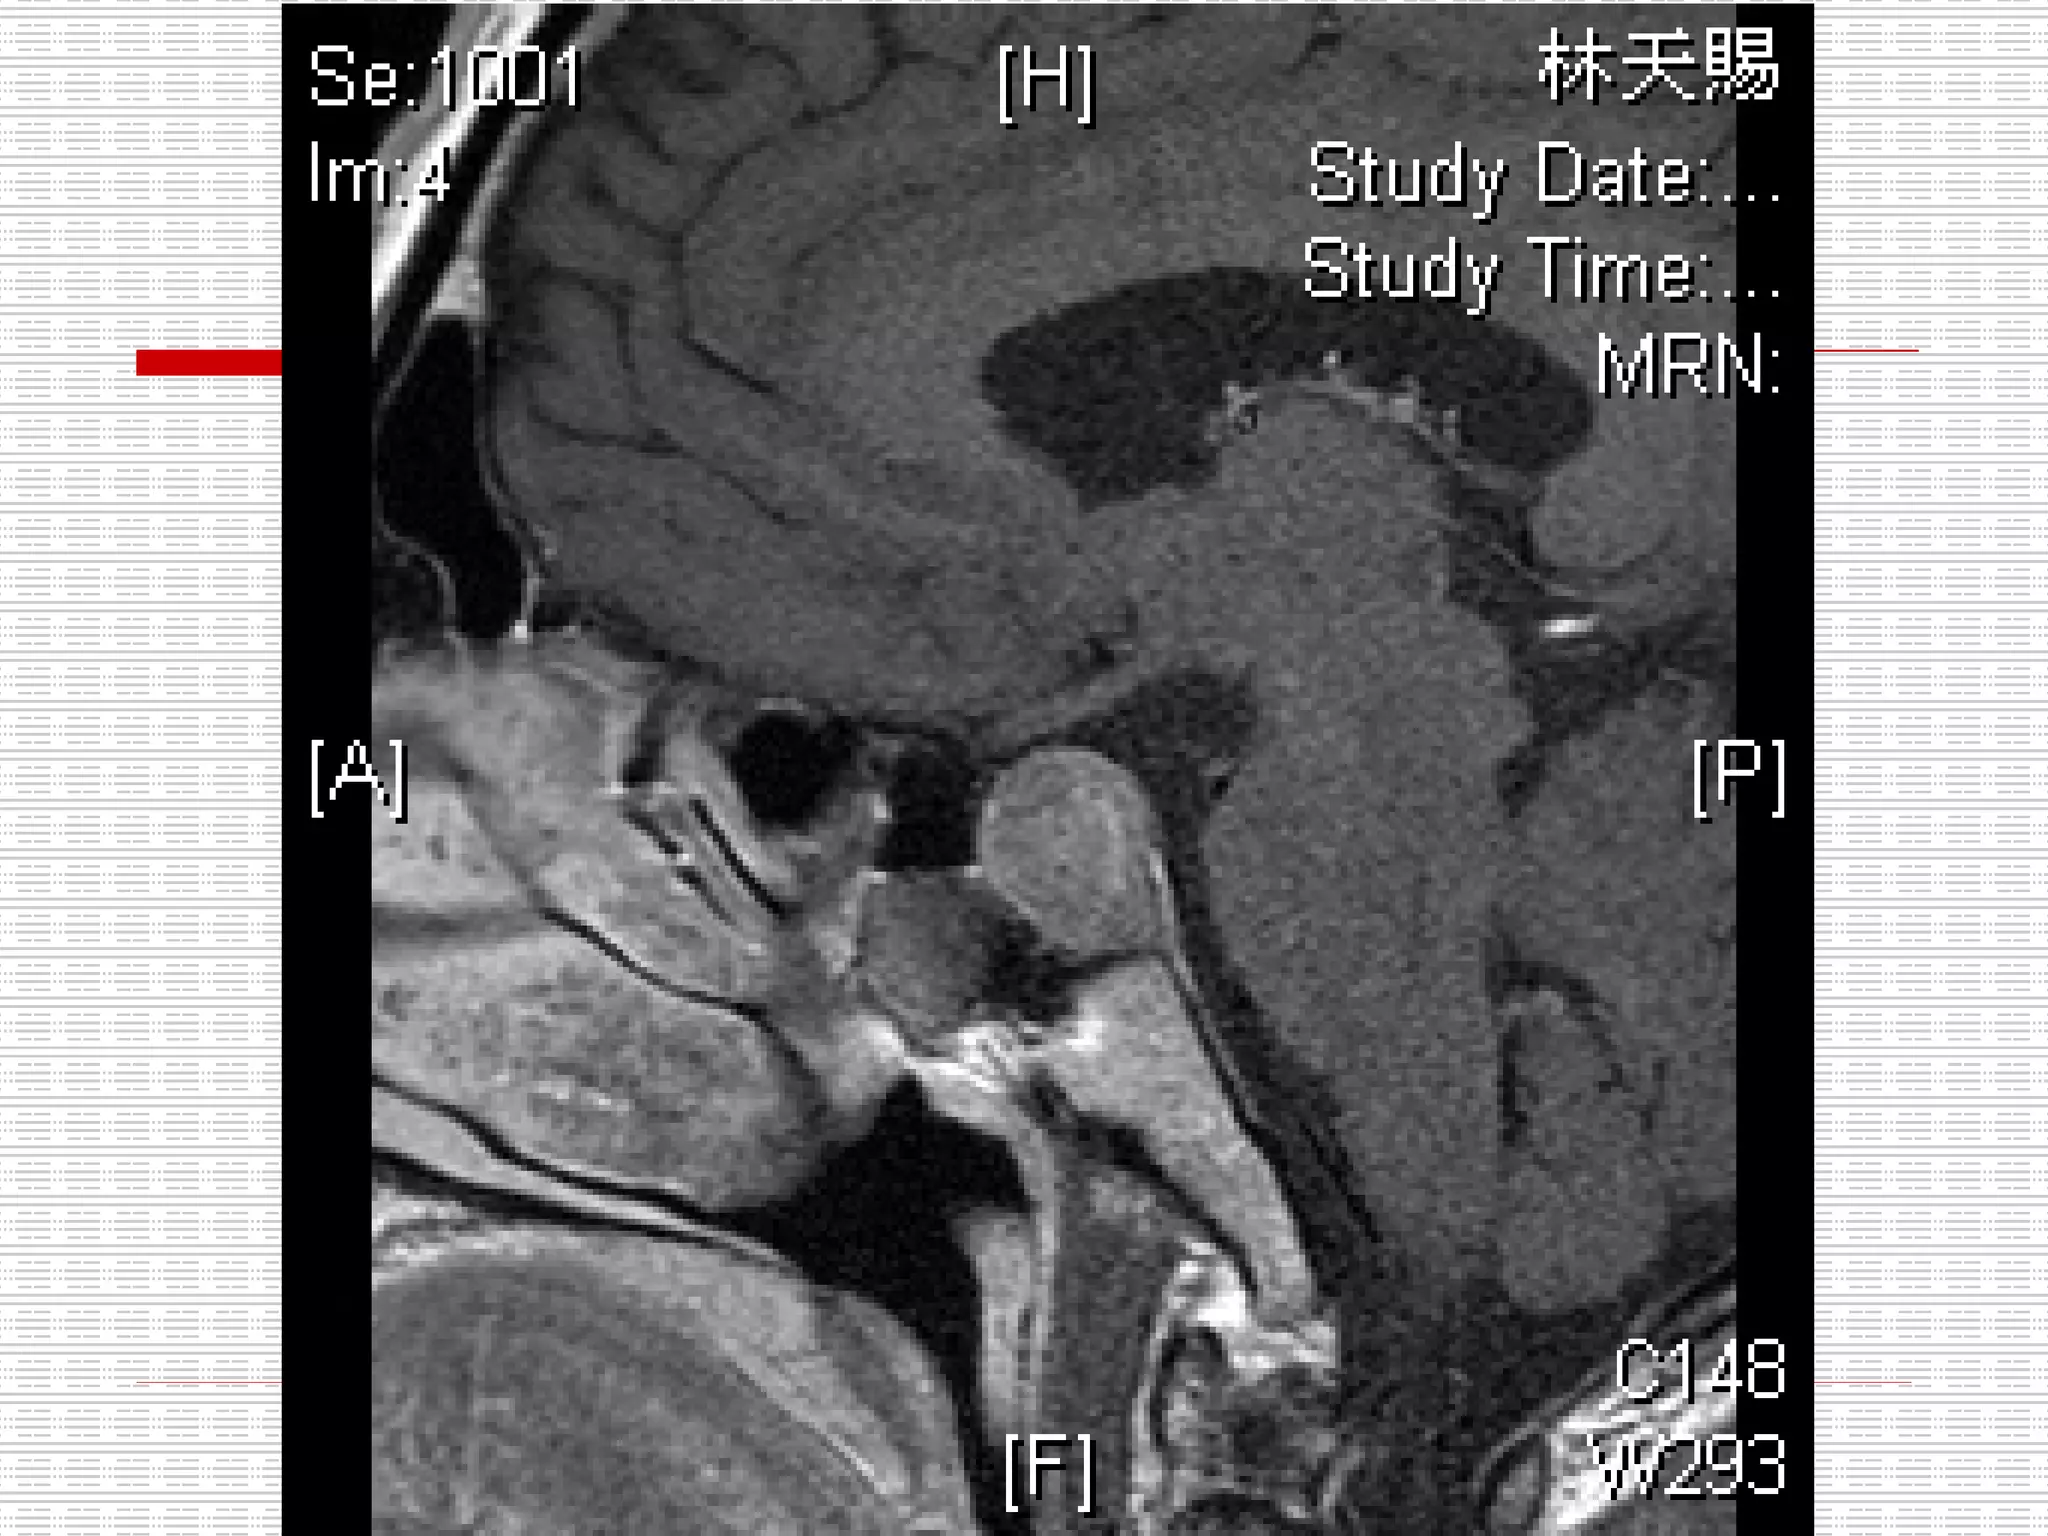

CT: Enlarged pituitary fossa with bony scalloping and soft tissue opacification

CT: Enlarged pituitaryfossa with bony scalloping and soft tissue opacification